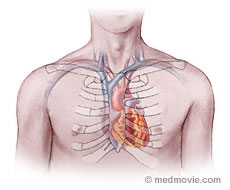

Анатомия Сердца: Расположение и Функции